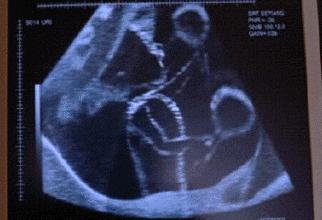

【孕7月:“看”到胎动】

怀孕7个月,羊水量比较大了,胎宝游起来就更舒心了,会多了很多踢腿的动作,而一些皮肤薄的孕妈,甚至直接能看到胎动,看着自己的肚子变形还真…蜜汁感觉。